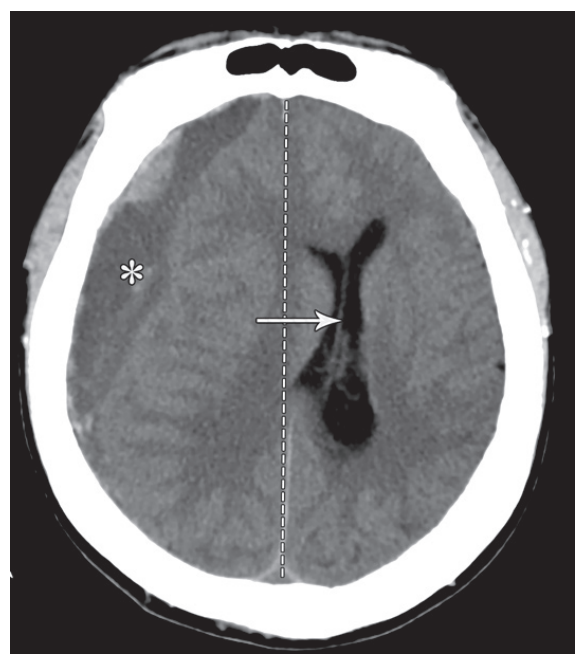

ct教学入门七大脑镰下疝

图片尺寸1724x1078

脑疝的类型及其影像学特点_医学界-助力医生临床决策和职业成长

图片尺寸578x761